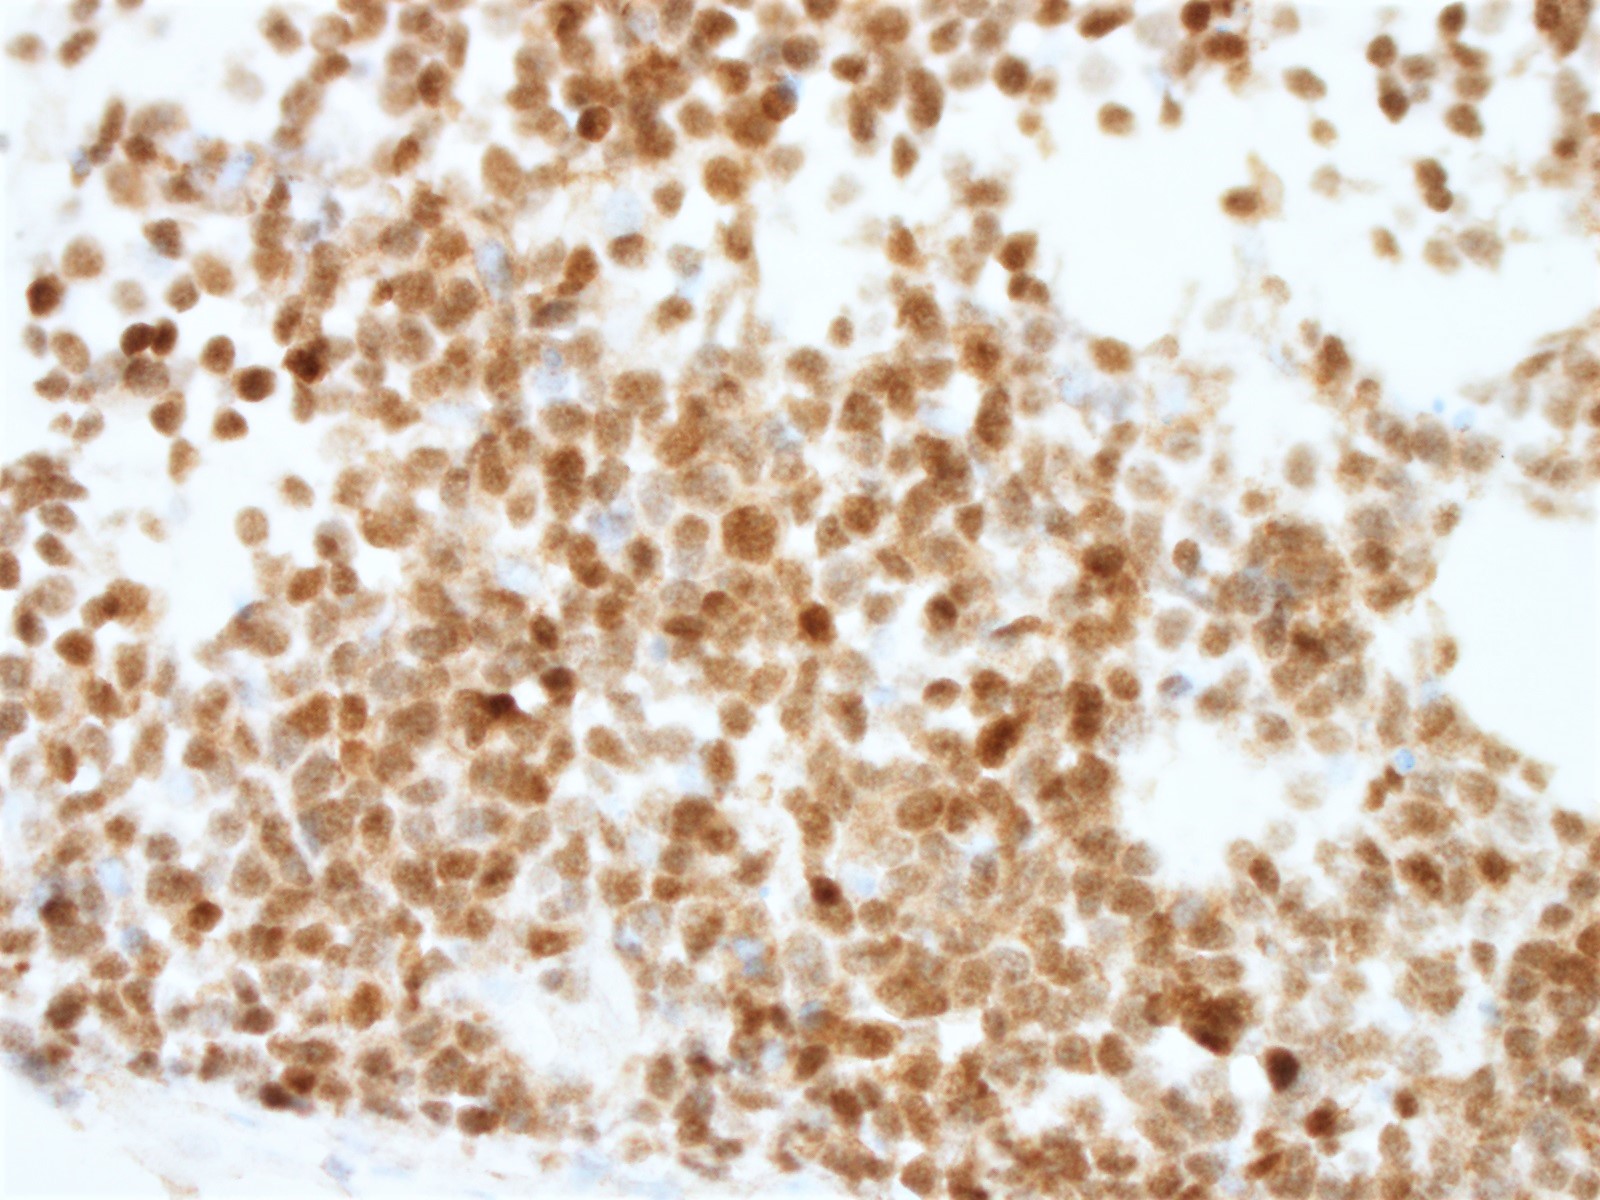

Microscopic (histologic) images

Positive stains

- Immunophenotype similar to classic mantle cell lymphoma

- Cyclin D1

- Ki67 count (J Hematop 2009;2:103)

- Note: Ki67 index is not sufficient to classify as blastoid or pleomorphic subtype

- Classical mantle cell lymphoma might also show high cell proliferation (Blood 2008;111:2385)